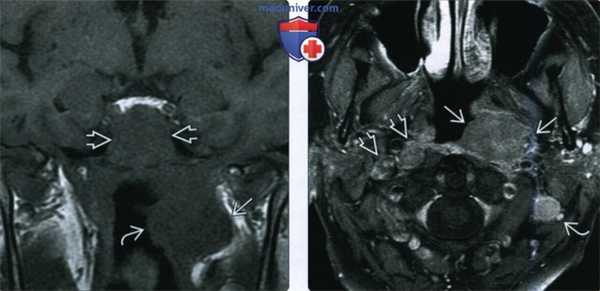

(Слева) При МРТ Т1C+FS b корональной проекции у женщины 65 лет с впервые выставленным диагнозом рака носоглотки в носоглотке слева визуализируется изъязвленное объемное образование В, накапливающее контраст; видны также некротически измененные ипсилатеральные лимфоузлы второго уровня. Были обнаружены и контрлатеральные лимфатические узлы. При исследовании биоптата подтвердился низкодифференцированный кератинизирующий плоскоклеточный рак.

(Справа) На комбинированной ПЭТ/КТ в корональной проекции определяется интенсивное накопление ФДГ в опухоли (рак) носоглотки слева и в лимфатическом узле второго уровня. Отдаленных метастазов обнаружено не было. Стадия опухоли в этом случае T2N2M0, третья стадия заболевания.г) Патология: